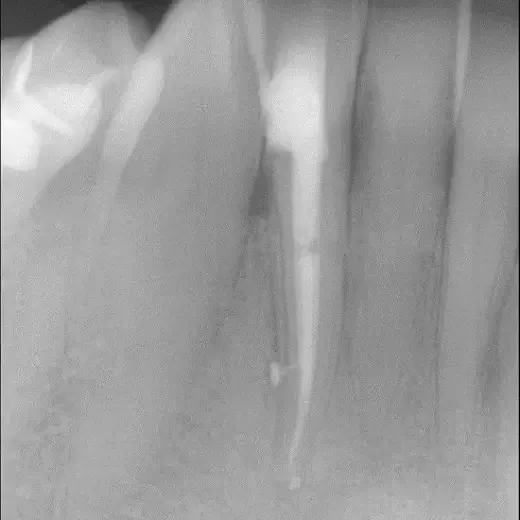

Fall 2: Entfernung eines Instrumentenfragmentes

Röntgenbild: Instrumentenfragment Ausgangssituation

Ausgangssituation

Röntgenbild: Instrumentenfragment Kontrolle nach Wurzelfüllung

Kontrolle nach Wurzelfüllung